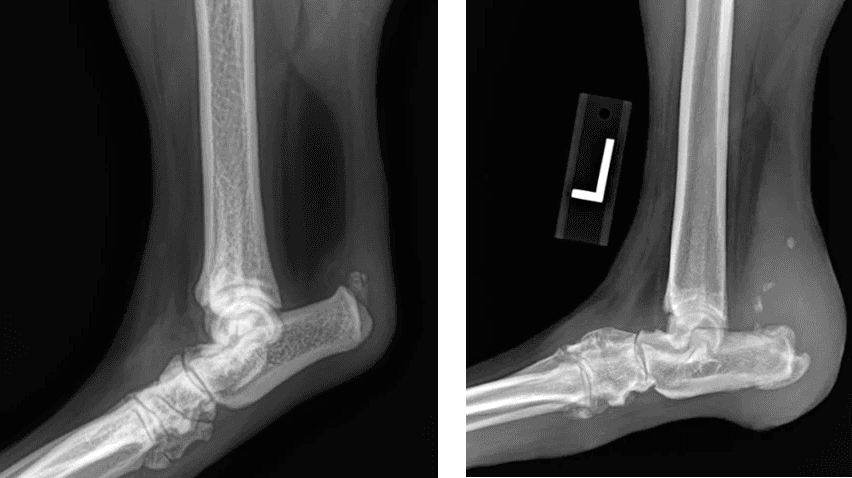

X-rays are recommended to rule out fractures and evaluate surrounding structures, although the diagnosis is often made based on examination findings alone.

Partial Achilles Rupture

Complete Achilles Rupture

X-ray changes with Partial and Complete Ruptures